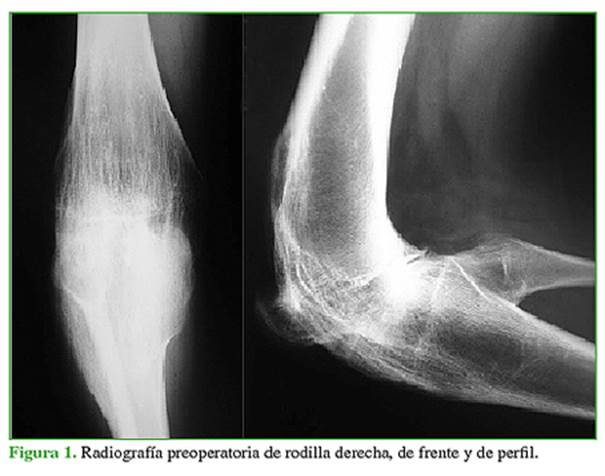

Mujer de 18 años, con artritis reumatoide juvenil y una intervención quirúrgica durante la infancia. Presenta anquilosis de la rodilla derecha en flexión de 100º, sin deformidad significativa en el plano coronal. En la rodilla izquierda, tiene un rango de movilidad de 90º, con una contractura en flexión de 30º. Tiene dificultad para deambular, subir y bajar escaleras y sentarse. El Knee Society Score (KSS) de la rodilla derecha medido antes de la cirugía era 26/50. En las radiografías, se puede observar la anquilosis ósea tanto tibiofemoral como rotulofemoral de la rodilla derecha (Figura 1).